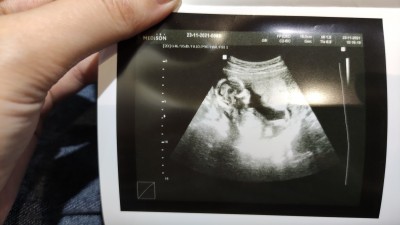

Cinsiyyet tahmini edermisiniz?Resimli

Erkekmi kızmı? Doktor söyledide tam emin diyil ama

15+5

%50kiz %50erkek:) hiç anlamam post yukarı ciksn

Dr erkek mi dedi bence erkek de :)

Evet erkek dedi) ama tam emin olmadı